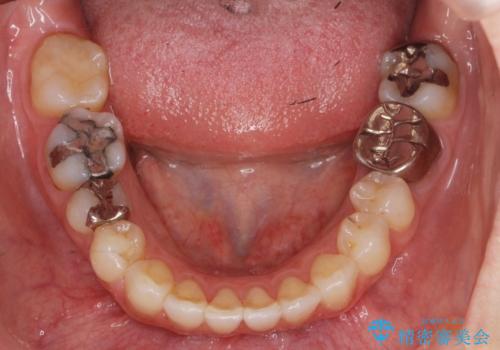

- 矯正治療後に虫歯治療を行いました。

左下7番には、矯正治療前に虫歯をとり、CRで充填していました。

また、左下6番は専門医(銀座院院長 Dr.林)による再根管治療を行いました。